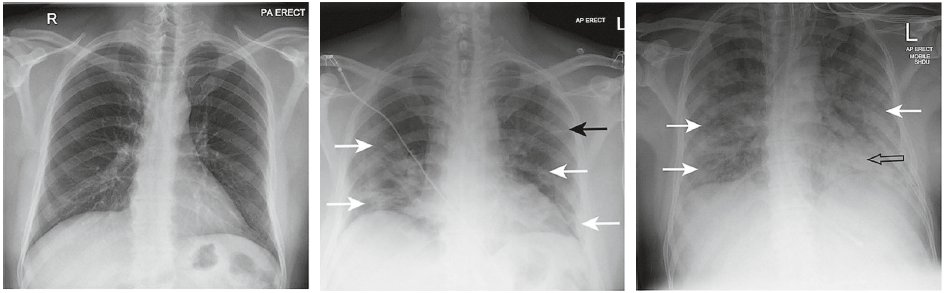

- Рентгенографія грудної клітки: щоб побачити те, чого не видно неозброєним оком.